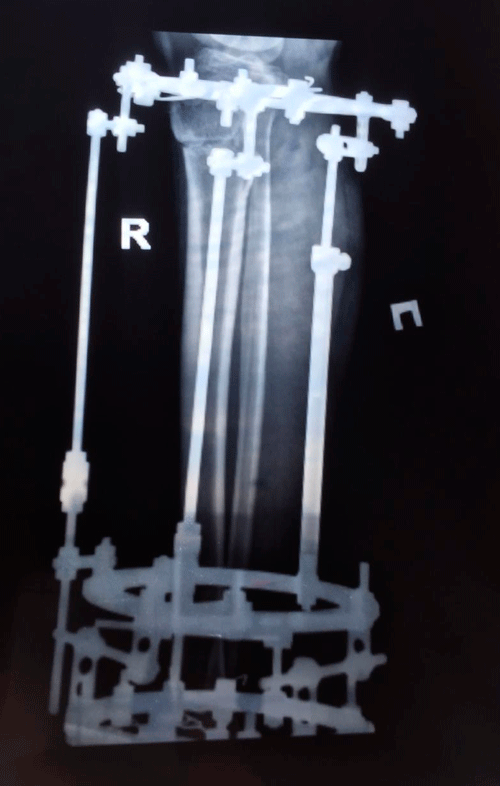

Рентген на фиксации(после исправления деформации ног)

IMG_1194-17-02-19-09-10.JPG